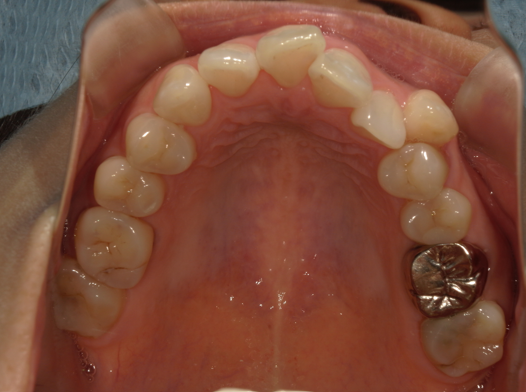

症例5:前歯のでこぼこが気になる

| 患者様データ | 10代 女性 |

| 来院主訴 | 前歯のでこぼこが気になる。 |

| 治療内容 | でこぼこを治すために上下の小臼歯を4本抜歯し、表側ワイヤー矯正を開始しました。かみ合わせを整えるためにゴムかけを行いました。 |

| 概算治療費 | 約80万円 |

| 治療期間 | 1年11ヶ月 |

| 通院回数 | 23回 |